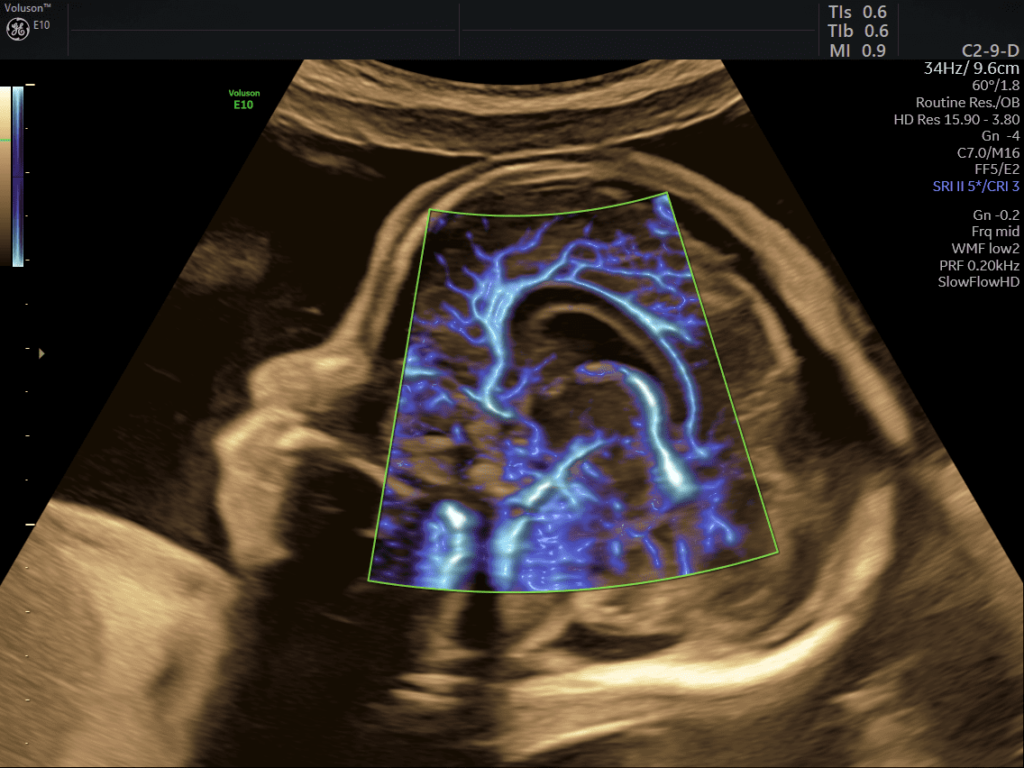

SlowflowHD™: software per lo studio della vascolarizzazione che grazie all’altissima sensibilità è in grado di sopprimere i movimenti a bassa frequenza preservando le informazioni sul flusso.